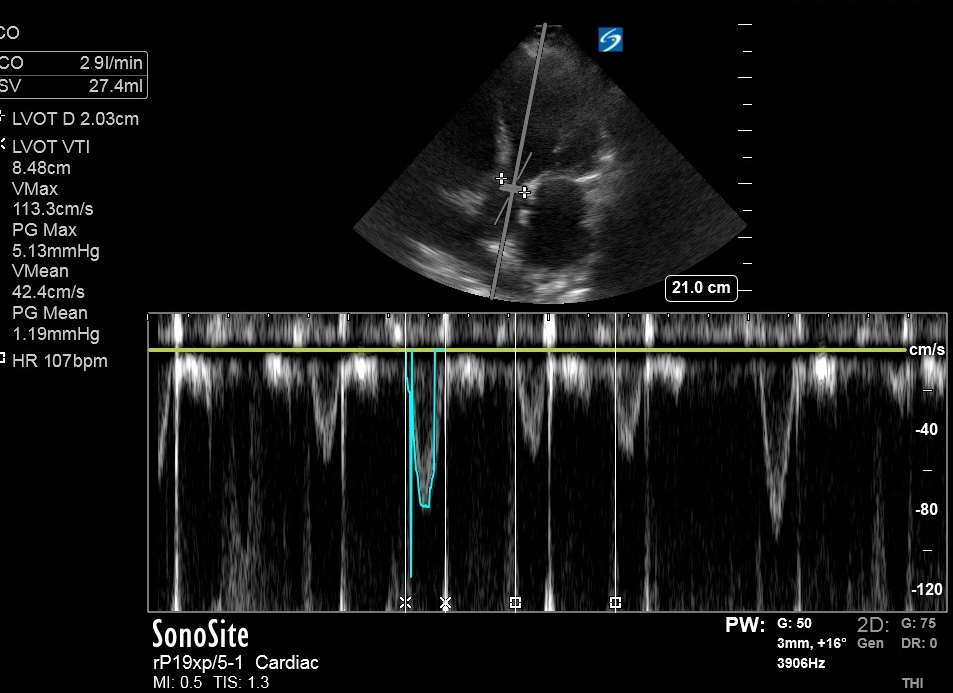

Bedside US done ~2 hours prior to RHC:

Bedside US done ~2 hours prior to RHC:

SVR estimated based on MRVmax/LVOT VTI ratio. (3.8/8.48) = 0.45

(>0.27 correlates with > 1120 dynes per onlinejase.com)

(>0.27 correlates with > 1120 dynes per onlinejase.com)